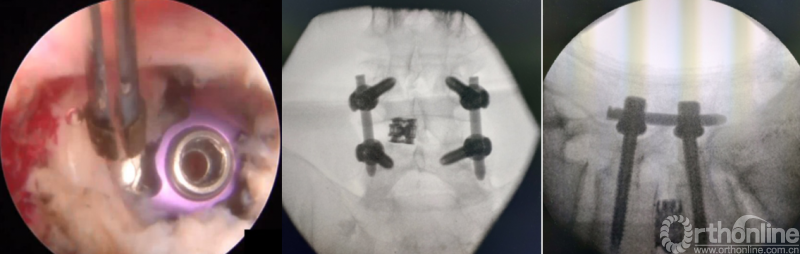

第七步“旋”:旋转舌形套管保护神经根;

第八步“铰”:盲视下可撑开铰刀置入,撑开并处理上下终板;

第九步“填”;椎间隙填塞植骨;

第十步“置”:置入融合器、经皮钉。